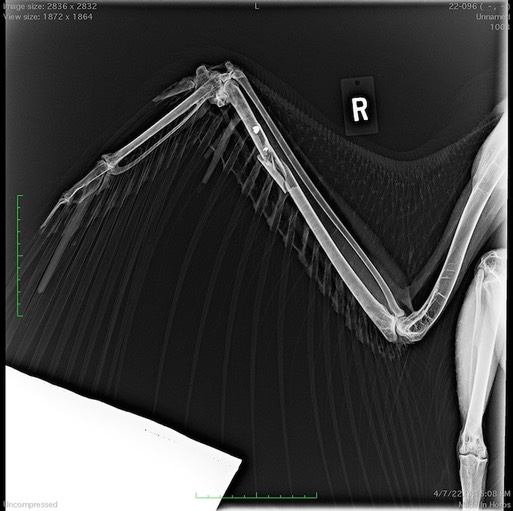

It seems like every week we see another gunshot bird. This week was no exception. An immature Bald Eagle was found near Yakima. It has an ulna fracture caused by a projectile which can be seen in the radiograph below.

The eagle’s wing has been immobilized. The hope is that the intact radius will act as a splint for the broken bone. The eagle is not a very happy patient!